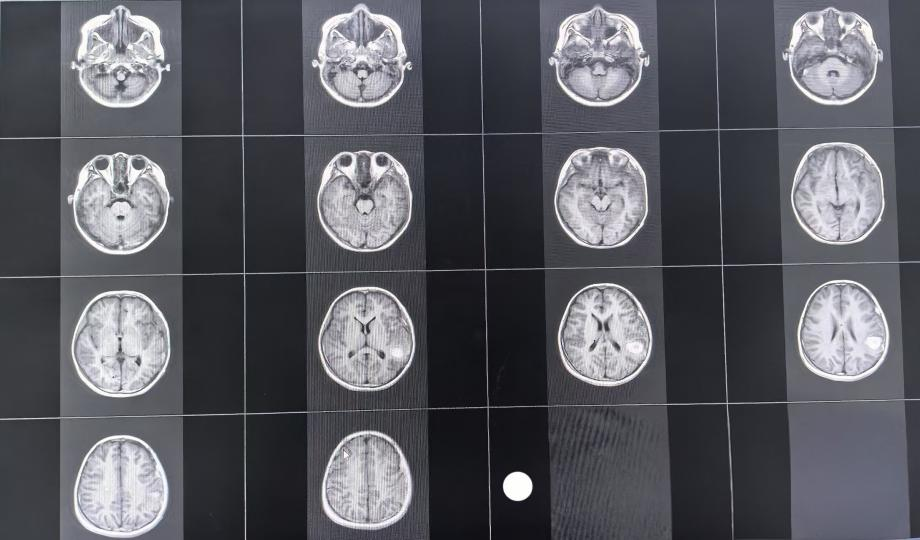

修补术前磁共振

修补术后CT

近年来,国际权威指南明确提出,在患者病情允许时,大力提倡早期开展颅骨修补术,即在颅脑损伤术后 3 个月内进行颅骨修补,这一举措被证实能显著改善患者预后。为此,神经外科一病区马小红主任医师团队,在深入分析患儿复杂病情、充分考量尽早实现临床治愈对患儿成长的重大意义,以及获得患儿家属高度肯定与信任后,在患儿术后40 天,为其实施颅骨修补术。

手术过程顺利,各环节衔接紧密。术后,患儿意识清晰,语言表达流畅,四肢活动自如,身体各项机能恢复良好,展现出早期颅骨修补术的显著成效,为同类病症的治疗提供了优质范例。